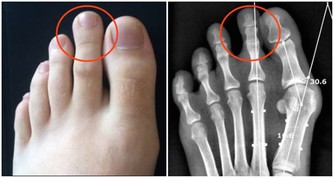

高血壓,是指以體循環動脈血壓(收縮壓和/或舒張壓)增高為主要特徵(收縮壓≥140毫米汞柱,舒張壓≥90毫米汞柱),可伴有心、腦、腎等器官的功能或器質性損害的臨床綜合徵。高血壓是最常見的慢性病,也是心腦血管病最主要的危險因素。